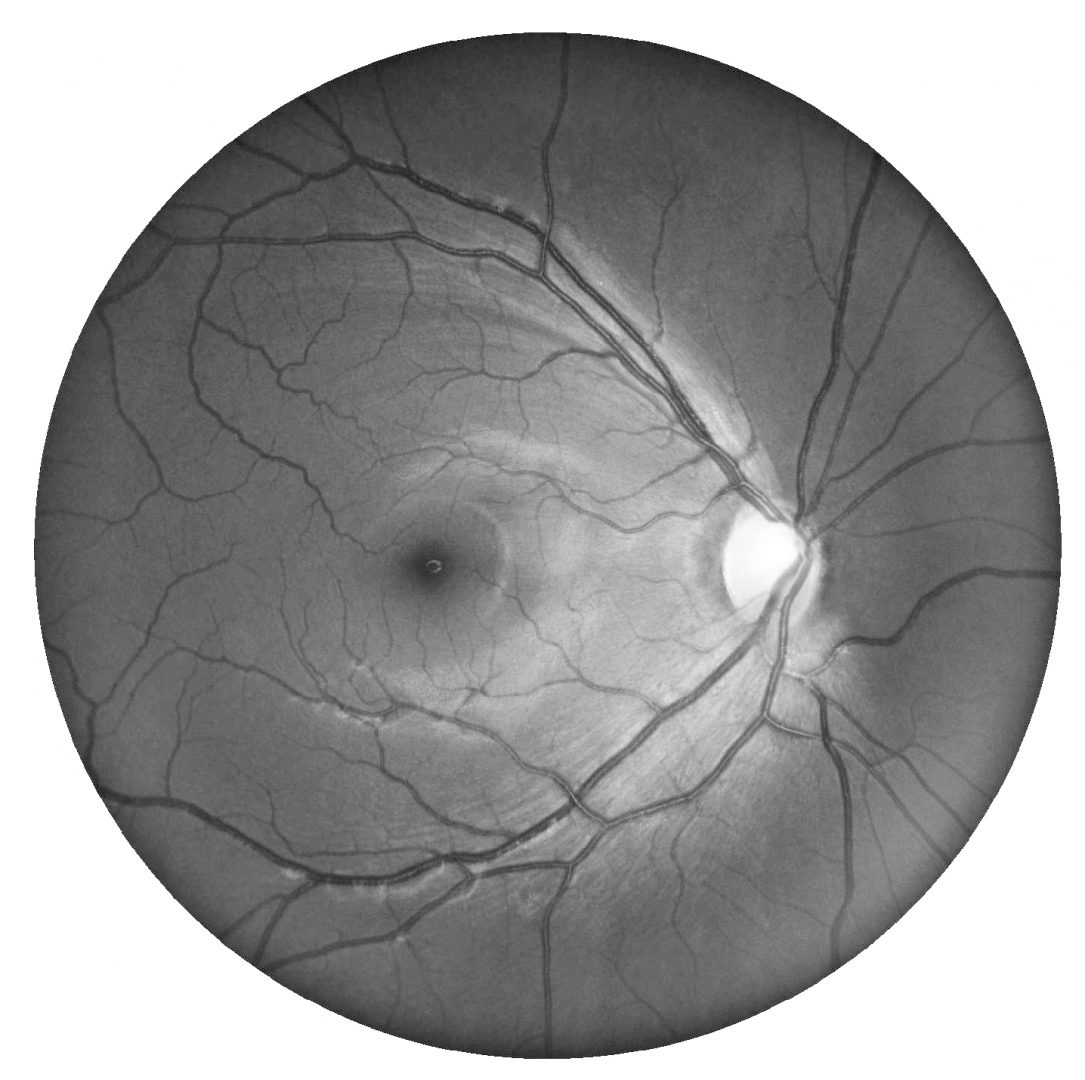

Funduscopically, a thinning of the RNFL and associated loss of the normal reflectivity is noted superiorly. Superior peripapillary atrophy and disc pallor with dense inferior altitudinal field defects are typically noted. Additionally, the superior branch of the central retinal artery enters the eye in a more superior location than is typical.

A 39 year old asymptomatic Asian male with best corrected visual acuity of 6/6 (20/20) in both eyes.

Retinal photo and red-free image (right and left eye)